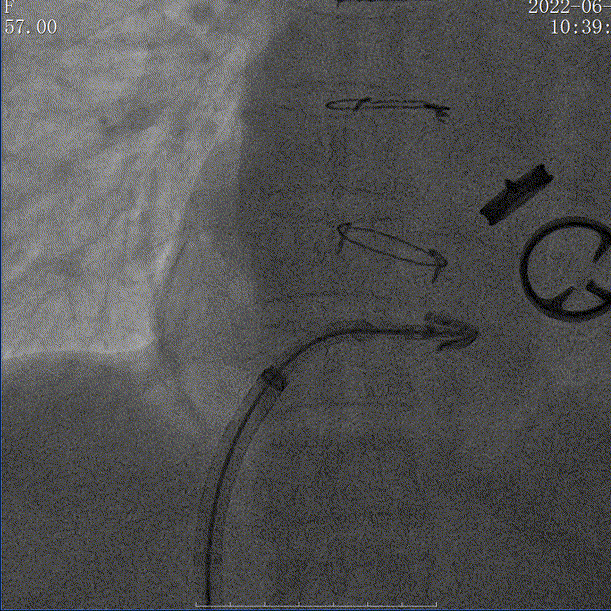

手术在经食道超声心动图和DSA引导下进行,使用KOKA CLAMP™经导管三尖瓣夹合器,经左侧股静脉穿刺,送入导丝建立右心房通路,送入三尖瓣夹合器械,在右心房调整双层控弯导管,将夹合器置于三尖瓣前叶与隔叶间反流最大区域,在DSA与TEE不断调整超声探头的角度和位置保证清晰的手术视野的双重指引下,进行瓣叶的捕获与夹合,在经食道超声心动图反复确认手术效果后,释放三尖瓣瓣膜夹。

术中DSA

术后DSA